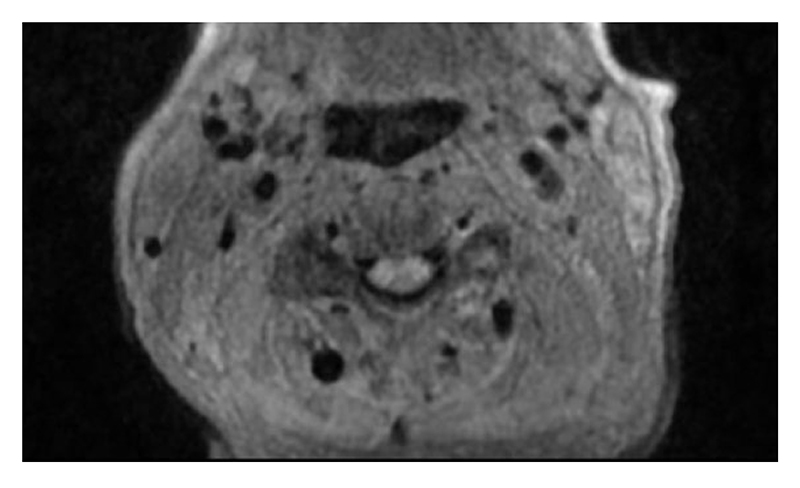

Magnetic resonance angiography (MRA) of the head and neck showed soft-tissue thickening of the distal left common carotid artery and left carotid bifurcation (Figure 1). A positron emission tomography (PET)-CT scan identified asymmetric moderate activity of the tracer fluorodeoxyglucose (FDG) along the medial aspect of the left common carotid artery (Figure 2). Skipped areas of mild uptake were also noted along the thoracic aorta wall.

Figure 2: PET-CT scan shows asymmetric hypermetabolic activity along the left common carotid artery.